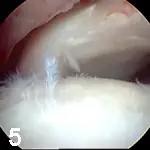

HipHip arthroscopy is an important part of our standard surgical evaluation of patients undergoing triple pelvic osteotomy (TPO). With arthroscopy, damage to articular cartilage or the labrum can be identified, which may alter the prognosis and is a contraindication for TPO (Figure 5).